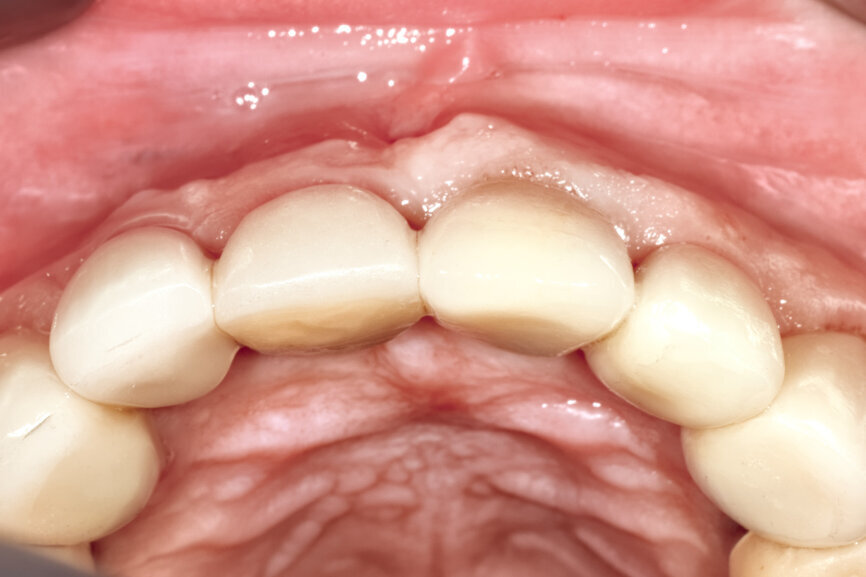

Fig. 26d: The soft-tissue contours were excellent; no sutures were required for the transitional restoration.

Fig. 30a: The occlusal view revealed the volume maintained with

the soft-tissue cervical contours (a), and the lateral retracted view revealed an excellent soft-tissue emergence profile (b).

Fig. 30b: The occlusal view revealed the volume maintained with

The initial plan was for immediate extraction, immediate placement and immediate restoration. Therefore, it was essential to measure the implant’s stability with an objective technology, RFA, which provides an ISQ value utilising an implant-specific SmartPeg (Osstell; MEGA ISQ, MegaGen). The baseline ISQ value (76) confirmed sufficient initial stability to place an immediate restoration (Fig. 25). The prefabricated CAD/CAM abutment was then secured to the implant, and a postoperative periapical radiograph confirmed successful sub-crestal placement for this platform-switched design (Fig. 26a). The transitional acrylic restoration was then placed and examined for any occlusal interferences (Fig. 26b). It was important that the restoration be out of occlusion to avoid premature forces that could complicate integration. The soft-tissue contours were excellent, and no sutures were required, since no flap was raised (Figs. 26c & d). After a period of eight weeks, the implant stability was measured to be at 80 ISQ, confirming that the integration process had continued to progress successfully and that the implant was ready for the definitive restoration. An intra-oral scanner and scanning abutment were then utilised to capture the position of the implant and soft-tissue emergence profile. The post- operative CBCT scan revealed the intact crescent shape of the root membrane (Figs. 27 & 28). The definitive restoration was then delivered and exhibited excellent retention of the soft-tissue profile (Figs. 29 & 30).